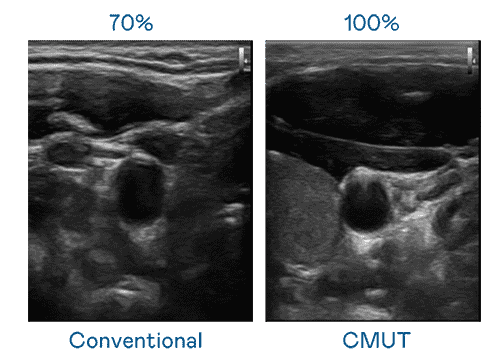

CMUT 技术是一种用电容式微机电元件来产生超音波讯号的技术。。。与传统 PZT 压电式技术相比,,,,CMUT 频宽增加 30%,,,,更宽频的超音波讯号让影像解析度大幅提升,,,,是实现高影像品质医疗超音波扫描、、促进精准医疗发展的关键技术。。。。

大频宽带来超清晰影像

超音波影像的解析度高低,,首先取决于探头能发出的讯号频宽。。。z6mg·人生就是博 CMUT 可提供高清晰的超音波讯号,,,提供高频宽、、、高灵敏度、、影像纹理细节更高的超音波影像,,,协助医护人员缩短影像判读时间及利用精准的医疗影像进行诊断。。。。